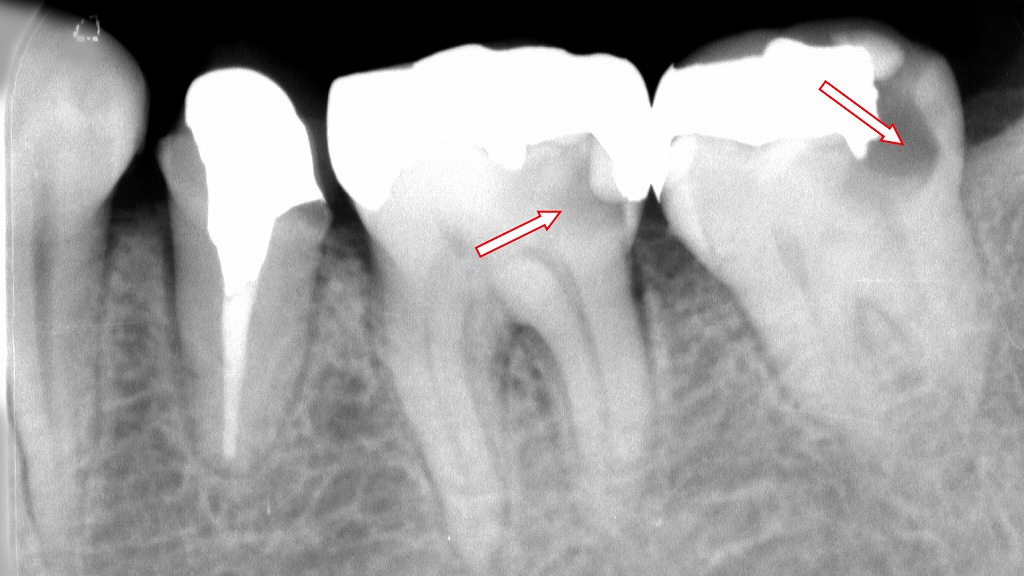

この画像は、下顎大臼歯部(第1大臼歯・第2大臼歯)を示すデンタルX線写真です。

赤い矢印で示された部分に、インレー(詰め物)の下にう蝕が認められます。

🔹所見の詳細

- 6番(左側の矢印)

詰め物(インレー)の下部、歯と修復物の境界部に黒く透けて見える領域があり、これは**二次う蝕(二次カリエス)を示唆します。

インレー装着時に軟化象牙質(虫歯が残っている部分)**の除去が不十分だった可能性があります。 - 7番(右側の矢印)

同様に、金属修復物の下に透過像(黒い影)が見られ、内部でう蝕が進行していると考えられます。

歯髄に近接しているため、症状によっては**根管治療(神経の治療)**が必要になることもあります。

🔹考えられる原因

- 修復時の軟化象牙質の取り残し

虫歯除去が不完全なまま修復した場合、内部で再び虫歯が進行します。 - インレーの適合不良

接着剤(セメント)の劣化や適合不良により、細菌が侵入して再感染します。 - 長期経過による劣化

古い金属修復物は辺縁封鎖性が低下しやすく、二次カリエスを起こしやすい傾向があります。

🔹治療と対策

- インレーを除去し、虫歯の範囲を確認したうえで軟化象牙質を完全に除去します。

- 必要に応じて、MTAセメントやコンポジットレジンによる裏層処置を行い、

再発防止のためには**精密な接着修復(セラミックインレーやダイレクトボンディング)**が望まれます。

このような症例は、見た目に問題がなくても内部で進行していることがあるため、定期的なレントゲン検査が早期発見に有効です。